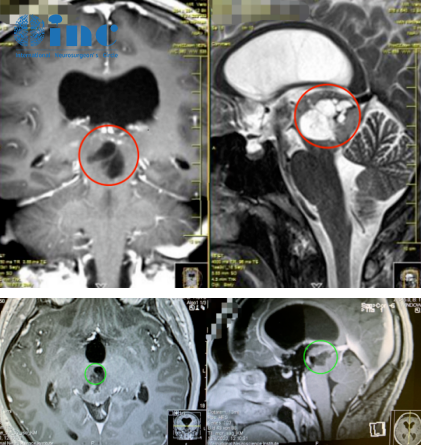

2019年,INC德国巴特朗菲教授曾4次来华,并在国内协作的三甲医院(苏州大学附属第一医院、苏州大学附属儿童医院、浙江大学医学院附属邵逸夫医院、无锡市第二人民医院等)开展疑难手术示范等,成功展示了多例在脑干、颅底、功能区等复杂病变(包括脑肿瘤/脑海绵状血管瘤/脑血管病变等)的全切及近全切手术之作。INC巴教授2019来华疑难手术示范掠影

2021年5月,INC排除万难推进“中德国际项目交流”,巴特朗菲教授来华进行学术交流及疑难手术示范。在上海市疫情防控办、江苏省卫建委、江苏省疫情防控办等政府相关部门的大力协助下,INC德国巴特朗菲教授来华计划得以成行,此次医学交流和疑难示范手术期间,两国医学专家同台手术,在救治疑难病症患者的同时,促成了中外神经外科之间的正常互动。

2021巴教授来华疑难手术示范掠影2022作为江苏省卫生支撑计划中德国际合作交流项目,INC国际神经外科医生集团旗下组织世界神经外科顾问团(WANG)成员、世界神经外科联合会WFNS教育委员会主席、德国INI国际神经学研究所Helmut Bertalanffy(汉莫特·巴特朗菲)教授受邀再次来华学术交流及疑难手术示范。在INC合作的国内三甲医院——苏州大学附属儿童医院及苏州独墅湖医院,巴特朗菲教授与国内专家同台示范手术,在救治疑难病症患者的同时,切磋手术技巧、学术交流讲学,推进中外神经外科之间的良性互动。

2022年巴教授来华疑难手术示范掠影